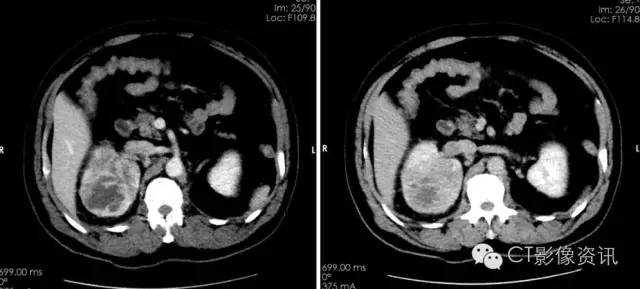

肾脏平扫:右肾上极可见混杂密度肿块影,边界模糊不清,形态不规则,未见明显钙化。

动脉期可见病灶明显强化,强化程度不均匀,实质内有低密度坏死区,边界欠清晰。